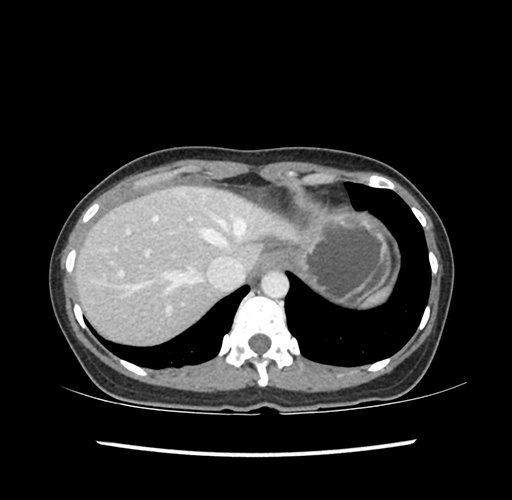

Imaging Analysis

Look through the patient's CT scan to identify any areas of concern for the necessary procedure.

Based on your CT findings, which issue(s) would give reason for "planned slowing down moment(s)" in this case?

Considering a standard left lateral sectionectomy procedure, what step(s) of the operation would you do differently in this case ?